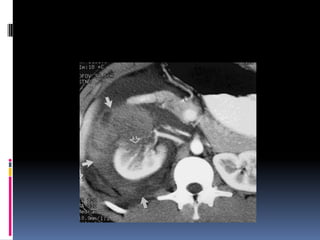

INJURIA HEPÁTICA

INJURIA HEPÁTICA Grados de severidad RadioGraphics 2009; 29:2033–2053